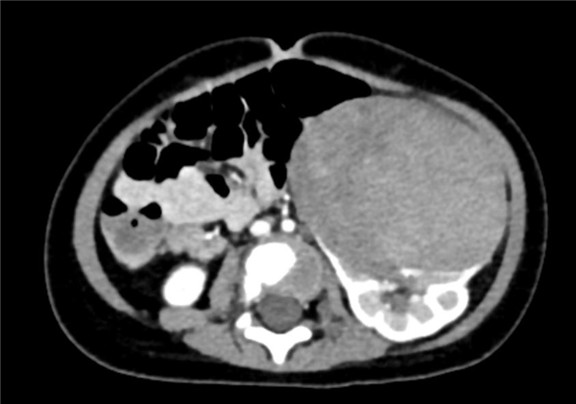

上腹部增强CT:左肾巨大占位性病变,疑似肾母细胞瘤

术前CT检查:

动脉期

静脉期

平衡期